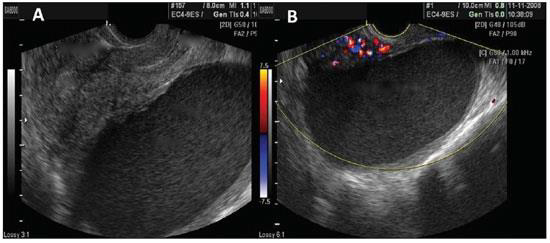

Paciente com quadro de infertilidade apresenta o seguiste achado ao ultrassom pélvico endovaginal (imagem anexa). Descrita como: "massa cística preenchida por ecos de baixa intensidade, de aspecto mais homogêneo que os cistos hemorrágicos e de parede bem delimitada. Sinal do "vidro moído". A massa foi abordada cirurgicamente, e quando se rompeu, saiu de sua cavidade uma substância similar à calda de chocolate. Trata-se provavelmente de um diagnóstico de: